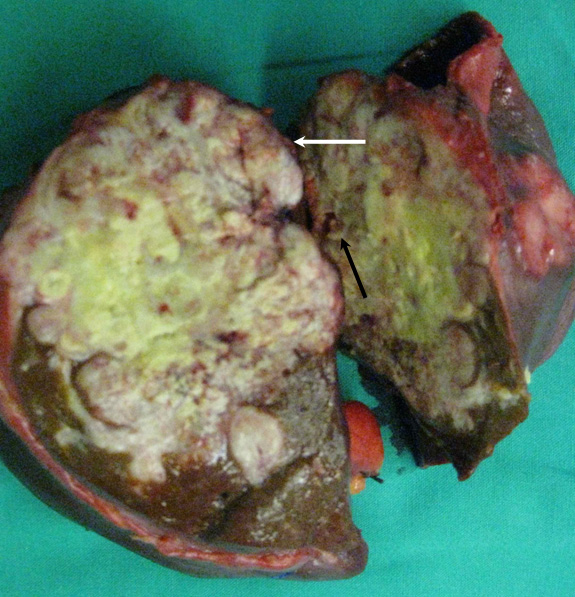

Μοναδική πιθανότητα θεραπείας αποτελεί η χειρουργική εξαίρεση σε υγιή όρια η οποία, στην περίπτωση του χολαγγειοκαρκινώματος, συνεπάγεται ηπατεκτομή (εικόνα 1). Για την εξαιρεσιμότητα λαμβάνονται υπ’ όψιν τρεις παράγοντες: 1) η επέκταση της νόσου στα χοληφόρα Β’ τάξης της δεξιάς ή της αριστερής πλευράς του ήπατος, 2) η επέκταση της νόσου στα προσαγωγά (ή απαγωγά) αγγεία της δεξιάς ή της αριστερής πλευράς του ήπατος και 3) η ατροφία της δεξιάς ή της αριστερής πλευράς του ήπατος (τροποποιημένο σύστημα σταδιοποίησης κατά MSK). Εφόσον ένας ή περισσότεροι από τους προαναφερόμενους παράγοντες βρίσκονται στην ίδια πλευρά του ήπατος, τότε το χολαγγεικοκαρκίνωμα είναι εξαιρέσιμο. Αν όμως ένας (ή και περισσότεροι) παράγοντες βρίσκονται σε διαφορετική ηπατική πλευρά, τότε το χολαγγειοκαρκίνωμα είναι μη εξαιρέσιμο. Η επέμβαση ξεκινά με λαπαροσκόπηση, γιατί στο 10% των περιπτώσεων ανακαλύπτεται διασπορά της νόσου που δεν είχε ανιχνευθεί από τις απεικονιστικές εξετάσεις. Αν και οι δυνητικά θεραπευτικές ηπατεκτομές για το χολαγγειοκαρκίνωμα είναι συνήθως εκτεταμμένες (με ή χωρίς πυλαίο εμβολισμό), η διεγχειρητική και μετεγχειρητική παρακολούθηση έχει εξελιχθεί σημαντικά, έτσι ώστε τα ποσοστά μετεγχειρητικού θανάτου μετά τη διενέργεια της βαρειάς αυτής επέμβασης να είναι χαμηλά (3% έως 7%). Η μεταμόσχευση για χολαγγειοκαρκίνωμα δε διενεργείται παρά μόνο κάτω από πολύ συγκεκριμένες προϋποθέσεις και μάλιστα εξαιρετικά σπάνια.

Εικόνα 1. Παρασκεύασμα αριστερής εκτεταμμένης ηπατεκτομής (τμήματα 1, 2, 3, 4, 5 & 8) για ενδοηπατικό χολαγγειοκαρκίνωμα.